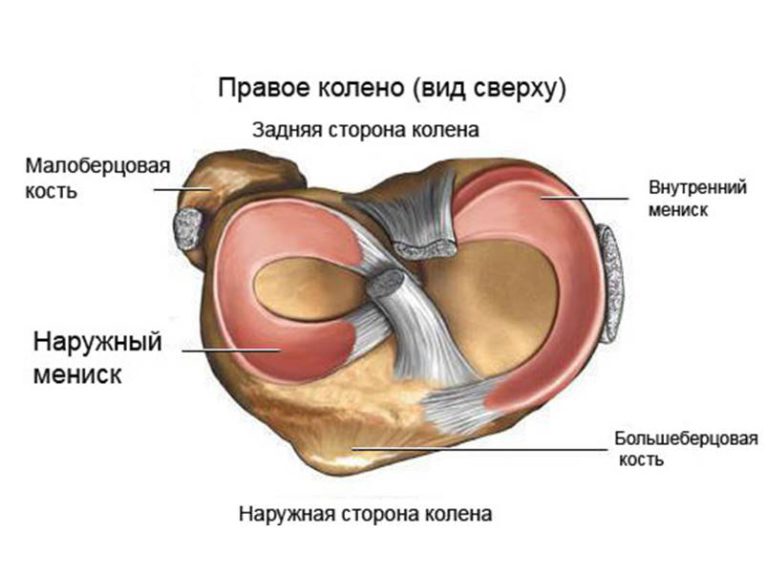

Супрапателлярный импиджмент коленного сустава: симптомы и лечение